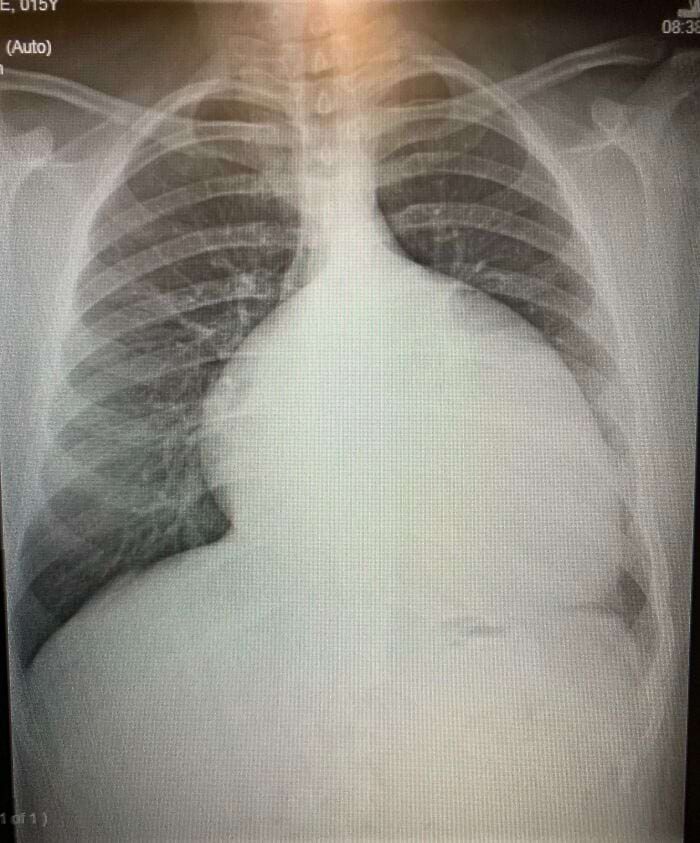

«Моё увеличенное сердце в 15 лет до операций»